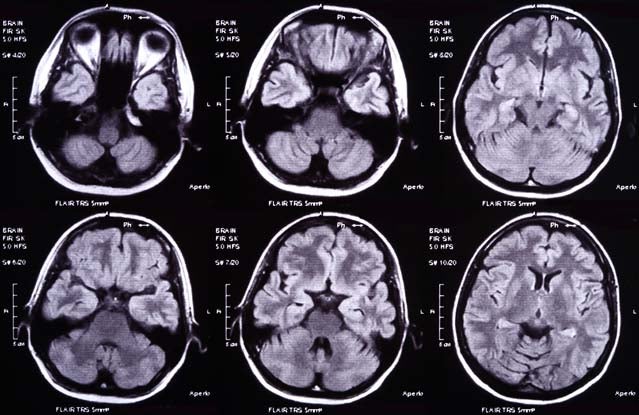

Head Injuries: More difficult than you think